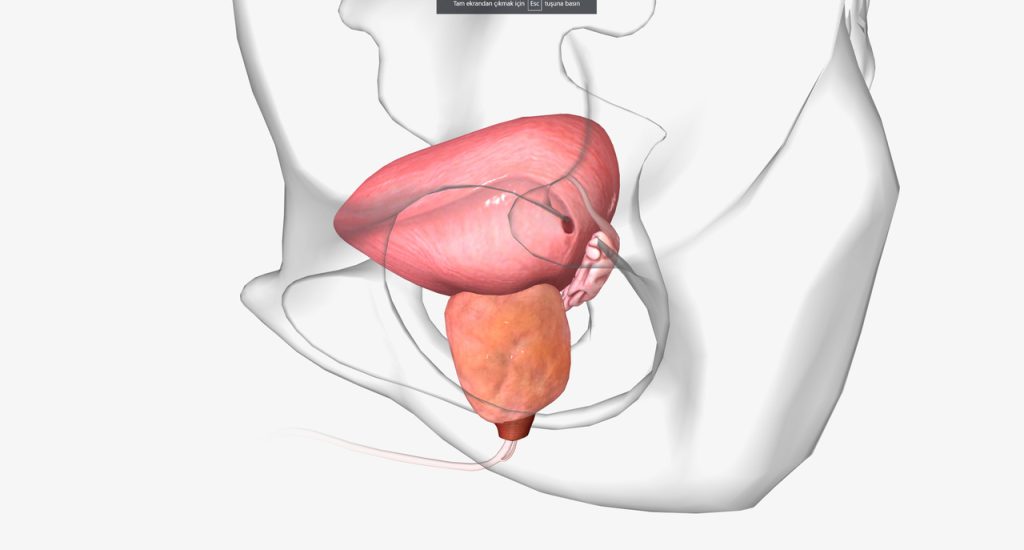

A Ressecção Transuretral da Próstata (RTU) é o procedimento indicado para o tratamento da próstata aumentada, uma condição que gera diversos problemas urinários como necessidade frequente e urgente de urinar, dificuldade em iniciar a micção, micção lenta, aumento da frequência de micção à noite, sensação de esvaziamento incompleto da bexiga.

Essa cirurgia tem duração entre uma hora e uma hora e meia. Nela, um ressectoscópio é inserido na ponta do pênis e estendido através da uretra para chegar na próstata. Depois, esse instrumento é usado para cortar o excesso de tecido prostático formando pequenos fragmentos, que por fim, são removidos.